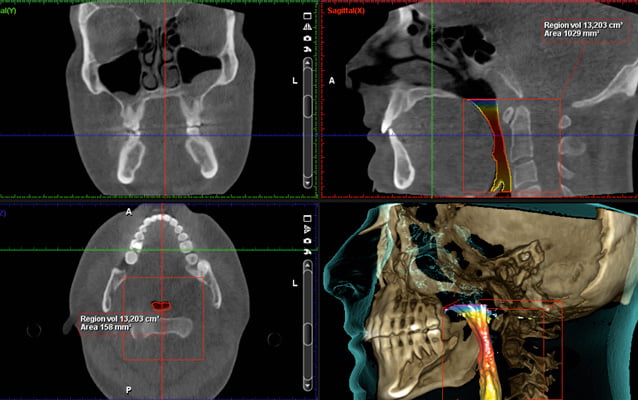

Protokół Planmeca Ultra Low Dose okazał się idealny do szerokiego zakresu zastosowań klinicznych, od ortodoncji do planowania implantów, chirurgii szczękowej oraz badań dróg oddechowych i zatok.

Planmeca Ultra Low Dose może być stosowany ze wszystkimi rozmiarami wokseli i wszystkimi trybami obrazowania, od najmniejszego rozmiaru woksela do największego pola widzenia (FOV). Ten protokół obrazowania jest idealny, gdy wymagane są szczegółowe informacje anatomiczne przy bardzo niskich dawkach promieniowania.

W pełni innowacyjny i naukowo zatwierdzony protokół obrazowania oparty na inteligentnych algorytmach 3D znacznie zmniejsza dawkę dla pacjenta bez pogorszenia jakości obrazu, zapewniając klinicystom na całym świecie możliwość skutecznego stosowania ALADY (minimalnej akceptowalnej diagnozy). Dążymy do tego, aby mieli taką możliwość. Stosowanie i skuteczność Donk Eye zostało naukowo zbadane i udowodnione w różnych badaniach.

Wysoka rozdzielczość i duża dawka nie zawsze są niezbędnymi standardami i często mniej znaczy więcej. Na przykład obrazowanie ultraniskodawkowe Planmeca jest niezbędne do uwidocznienia kanału nerwu żuchwowego przy planowaniu implantów i ekstrakcji zębów mądrości. Wszystko to można osiągnąć przy wyjątkowo niskich dawkach.